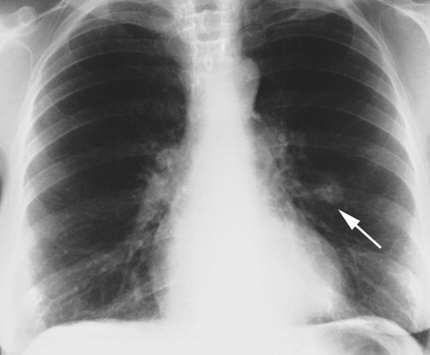

Із-за того що патологія переважно протікає безсимптомно, виявити її вдалося тільки під час профілактичного огляду. Для отримання більш детальної клінічної картини лікар призначає рентгенологічне дослідження, при якому виявляються тіні округлої форми різних розмірів з рівними або хвилястими контурами. Зазвичай на рентгенограмах визначають вапняні включення. Їх кількість обумовлена інтенсивністю тіні. Якщо проводити тривале динамічне дослідження, можна помітити, що у розмірах гамартома легкого змінюється дуже повільно. З іншого боку, інтенсивність вапняних відкладень швидко прогресує.

Освіти ендобронхіальной природи виявляються прямими та непрямими ознаками. У першому випадку мова йде про сферичної пухлини з рівними і чіткими краями, що виявляються за допомогою рентгенологічного дослідження. Непрямі прояви — це ателектаз, гіповентиляція і інші ознаки, що вказують на порушення бронхіальної провідності.